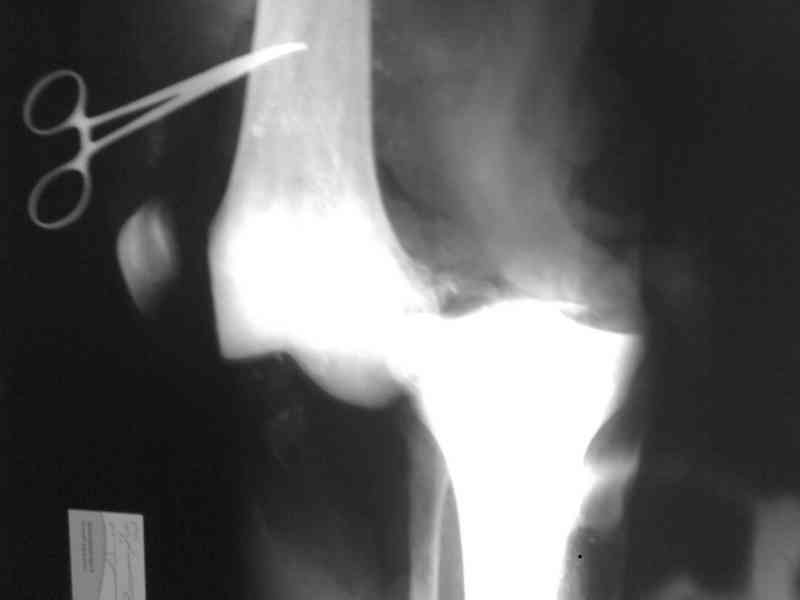

На ренгенограмме хорошая аппозиция костей коленного сустава, но надколенник находится подозрительно высоко, поэтому необходимо убедиться в отсутствии повреждения связки надколенника.

Наличие пульсации на конечностях еще не доказательство отсутствия интимальных повреждении сосудов, наблюдались вторичные осложнениия, поэтому важна консультация сосудистого специалиста.

Снимки прошлых публикации из моего Power point